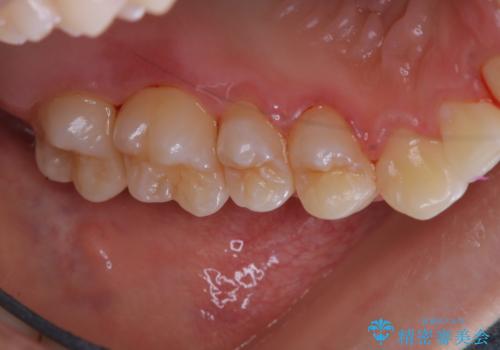

- しばらく歯科でのメンテナンスを受けていないため、歯磨きのチェックとクリーニング希望とのことで来院されました。

染め出しをしてのブラッシング指導とPMTCを行いました。